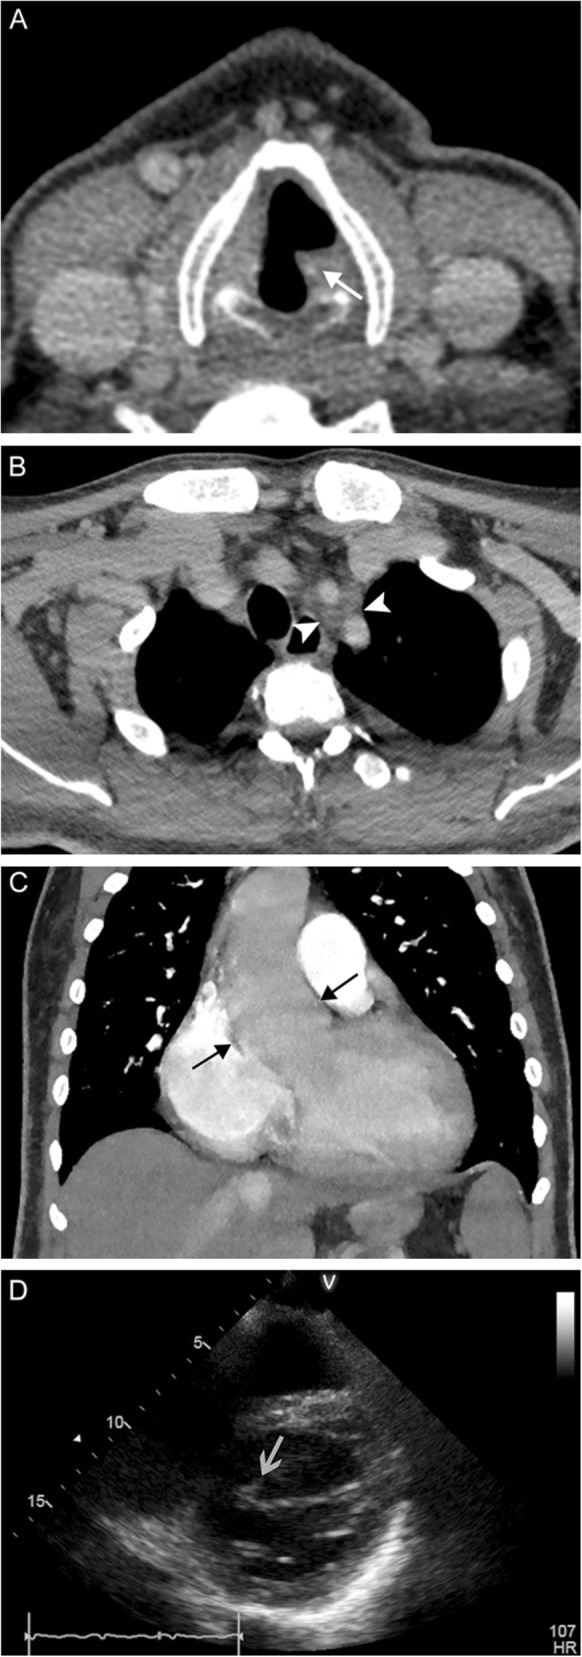

Fig. 21.

Endocarditis. A 41-year-old previously healthy man presents with intermittent hoarse voice and unexpected weight loss. Axial contrast-enhanced CT images through the larynx (a) and mediastinum (b) reveal left vocal fold rotation (white arrow) and lymphadenopathy surrounding the left carotid and subclavian arteries (white arrowheads). A coronal CTA image (c) reveals an ascending aortic aneurysm (black arrows). Echocardiogram (d) reveals a bicuspid valve with vegetations (gray arrow) and severe aortic stenosis. Overall, findings are consistent with compression/stretching of the left recurrent laryngeal nerve due to reactive lymphadenopathy and a dilated aortic arch in the setting of endocarditis

Fig. 22.

Pulmonary artery aneurysm. A 78-year-old man with advanced congestive heart failure secondary to congenital pulmonary artery stenosis status post multiple corrective surgeries, now presenting with progressive shortness of breath and speaking difficulty despite adequate management of heart failure. Axial CTA image (a) through the mediastinum reveals aneurysmal dilatation of the left pulmonary artery (white arrows). An axial CTA image through the larynx (b) reveals thickening of the left aryepiglottic fold (white arrowhead) and dilatation of the left piriform sinus (black arrow). A coronal CTA image (c) demonstrates effacement of the aortopulmonary window (black arrows) by the pulmonary artery aneurysm (white arrows) with presumed compression of the left recurrent laryngeal nerve